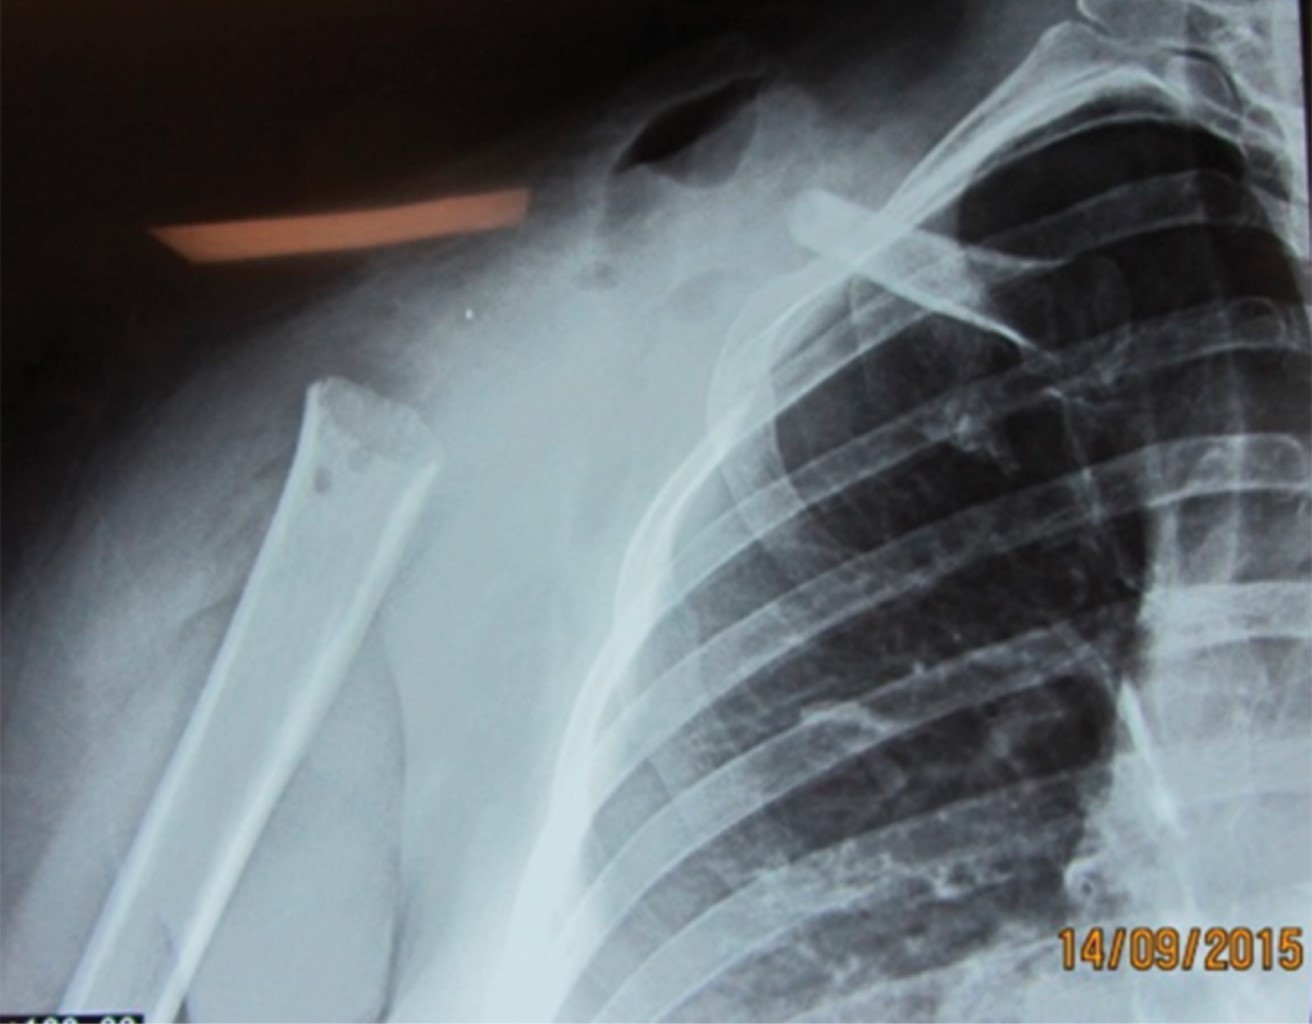

La incidencia del caso es 2-5:1'000,000, por lo que representa una rareza diagnóstica. En estudios donde se reporta el uso de la técnica de Tikhoff-Linberg tipo 410,11 se utilizan prótesis de escápula y/o húmero (Figura 7), en este caso se realizó una variable quirúrgica sin el uso de prótesis, por lo que se procedió a "anclar" el húmero de la clavícula residual por medio de sutura de poliéster (Figura 3), técnica de la que, a pesar de ser descrita por Linberg,8,11 no existen casos publicados sobre su uso. Se presenta radiografía posterior al procedimiento (Figura 8).